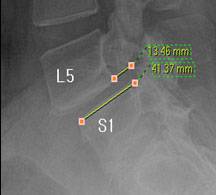

모커리한방병원 위 뼈가 50%정도 밀려나간 모습 이미지

척추전방전위증은 척추 주변, 특히 척추 후방에 있는 후관절 주변의 근육과 인대 그리고 후관절 자체가 퇴행되어 척추 뼈를 제대로 붙잡아 주지 못해 위아래 척추 뼈가 앞뒤로 밀려 나가면서 발생하는 척추질환을 말합니다.